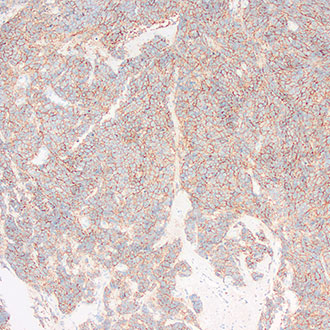

CD45

CD45 -